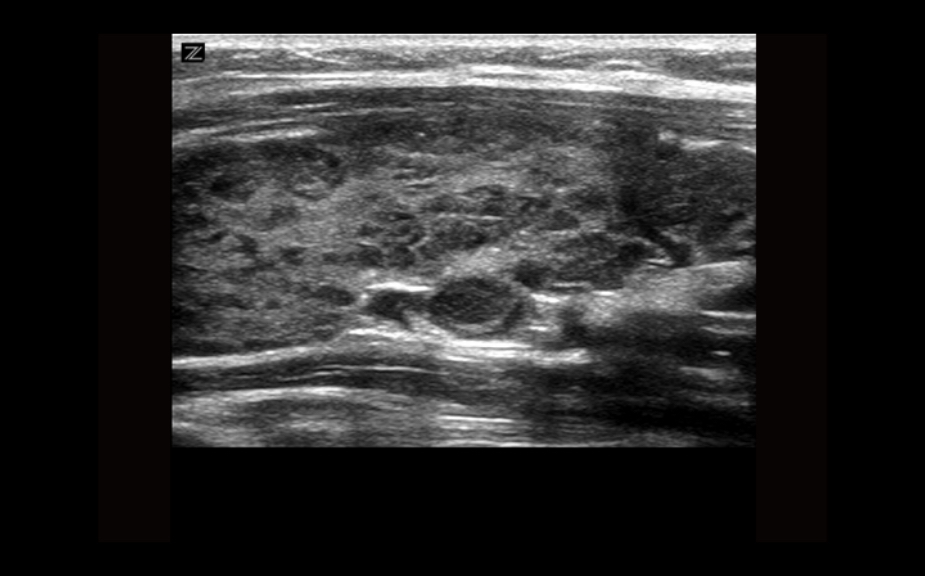

Equipped with patented, software based ZONE Sonography? Technology (ZST), the Z.One PRO provides optimally detailed B-mode and Doppler imaging for patients, regardless of body habitus, helping assure a reliable diagnosis.

Throughout a wide range of applications, the Z.One PRO is the ultrasound solution for your demanding clinical challenges.

- Unsurpassed image quality across all applications

The Z.One PRO ultrasound imaging platform offers a complete family of lightweight transducers that feature both extended broadband capabilities and multi-frequency flexibility delivering exceptional clarity and enhanced detail resolution even at the deepest depths. The C4-1 transducer can penetrate throughout the field of view while maintaining exception spatial and contrast resolution.